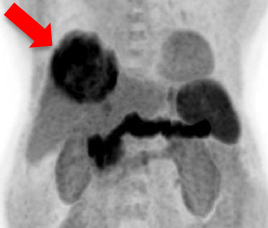

- 治療前雙示踪劑正電子/電腦雙融掃描

- 識別代謝異質性因子

- 分類細胞分化

- 劃定輻射敏感性

- 肝臟腫瘤因代謝高、體積大而不適宜手術治療

- 甲胎蛋白水平是2269 ng/ml

C-11 Acetate F-18 FDG